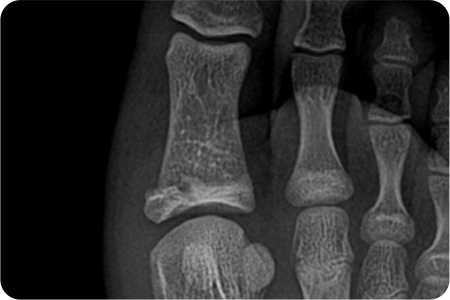

발가락 골절은 대부분 보존적 치료(깁스, 테이핑)로

회복되지만, 골절이 심하거나 뼈가 크게 어긋난 경우,

관절을 침범한 경우, 분쇄 골절에서는 수술이 필요합니다.